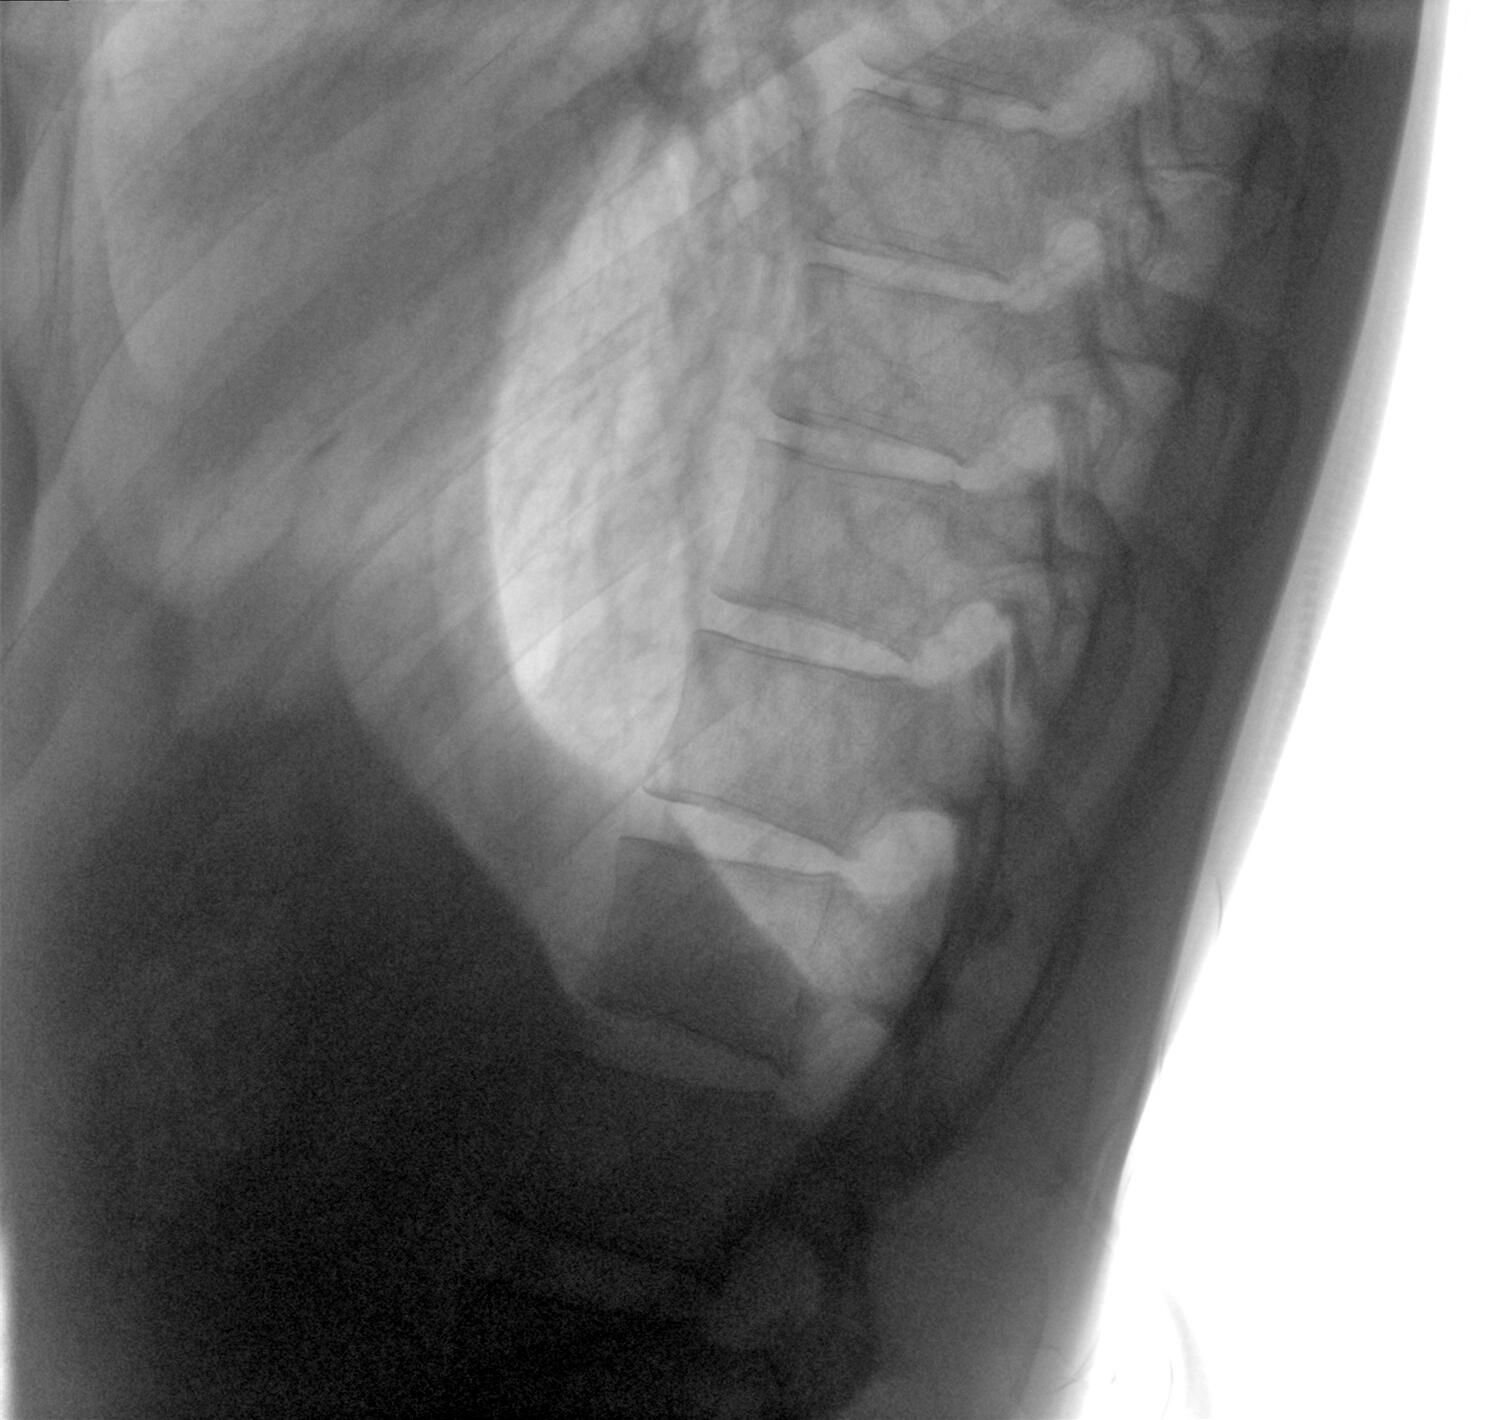

配備了兩種平板尺寸,大尺寸動(dòng)態(tài)平板探測(cè)器成像面積較傳統(tǒng)平板探測(cè)器提升了25%以上,在視野需求大的手術(shù)中,便于醫(yī)生更好定位病灶點(diǎn),規(guī)劃手術(shù)方案,減少因視野范圍不足而多次透視、點(diǎn)片造成的不便,不僅提高了手術(shù)效率,也減少了輻射劑量。